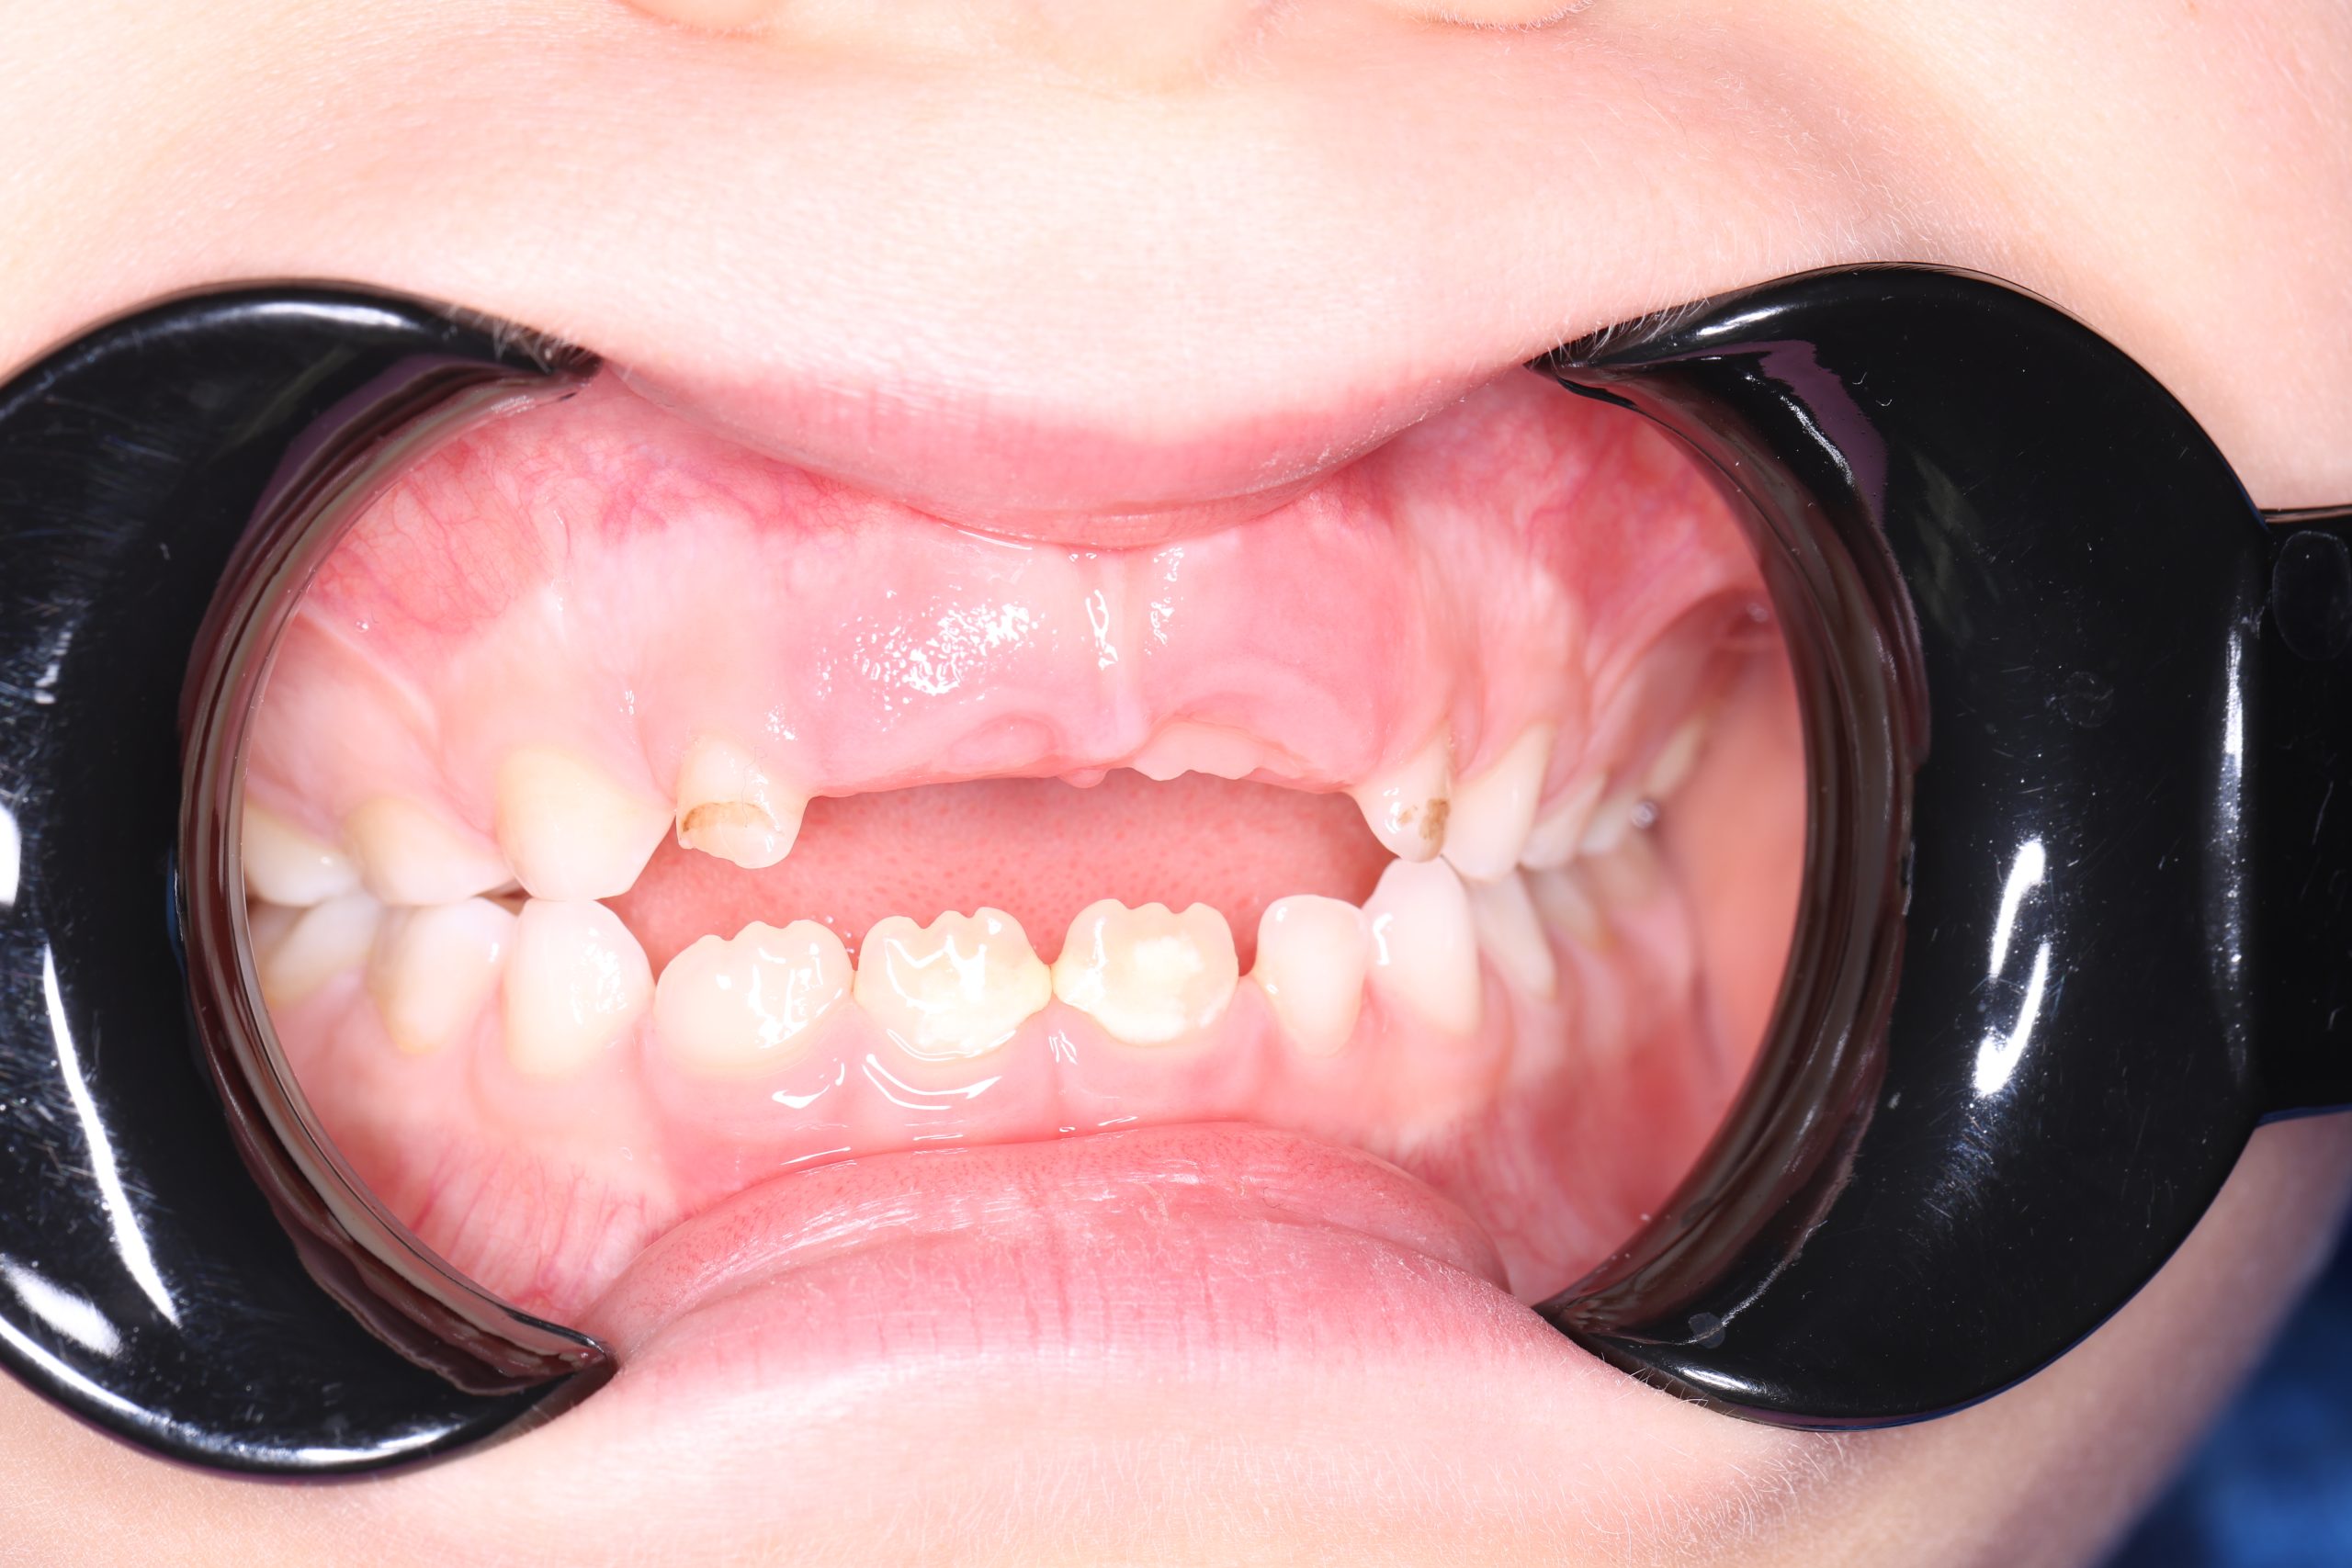

- Detailed Examination

We examine the condition of teeth, gums, and bite. - Plaque Disclosure with Special Indicators

Any tartar is removed gently and painlessly. - Final Check-Up + Fluoride Protection

We ensure the teeth are clean and free from early caries (even in the spot stage), then apply fluoride varnish to protect and strengthen enamel. - Personalized Recall Plan